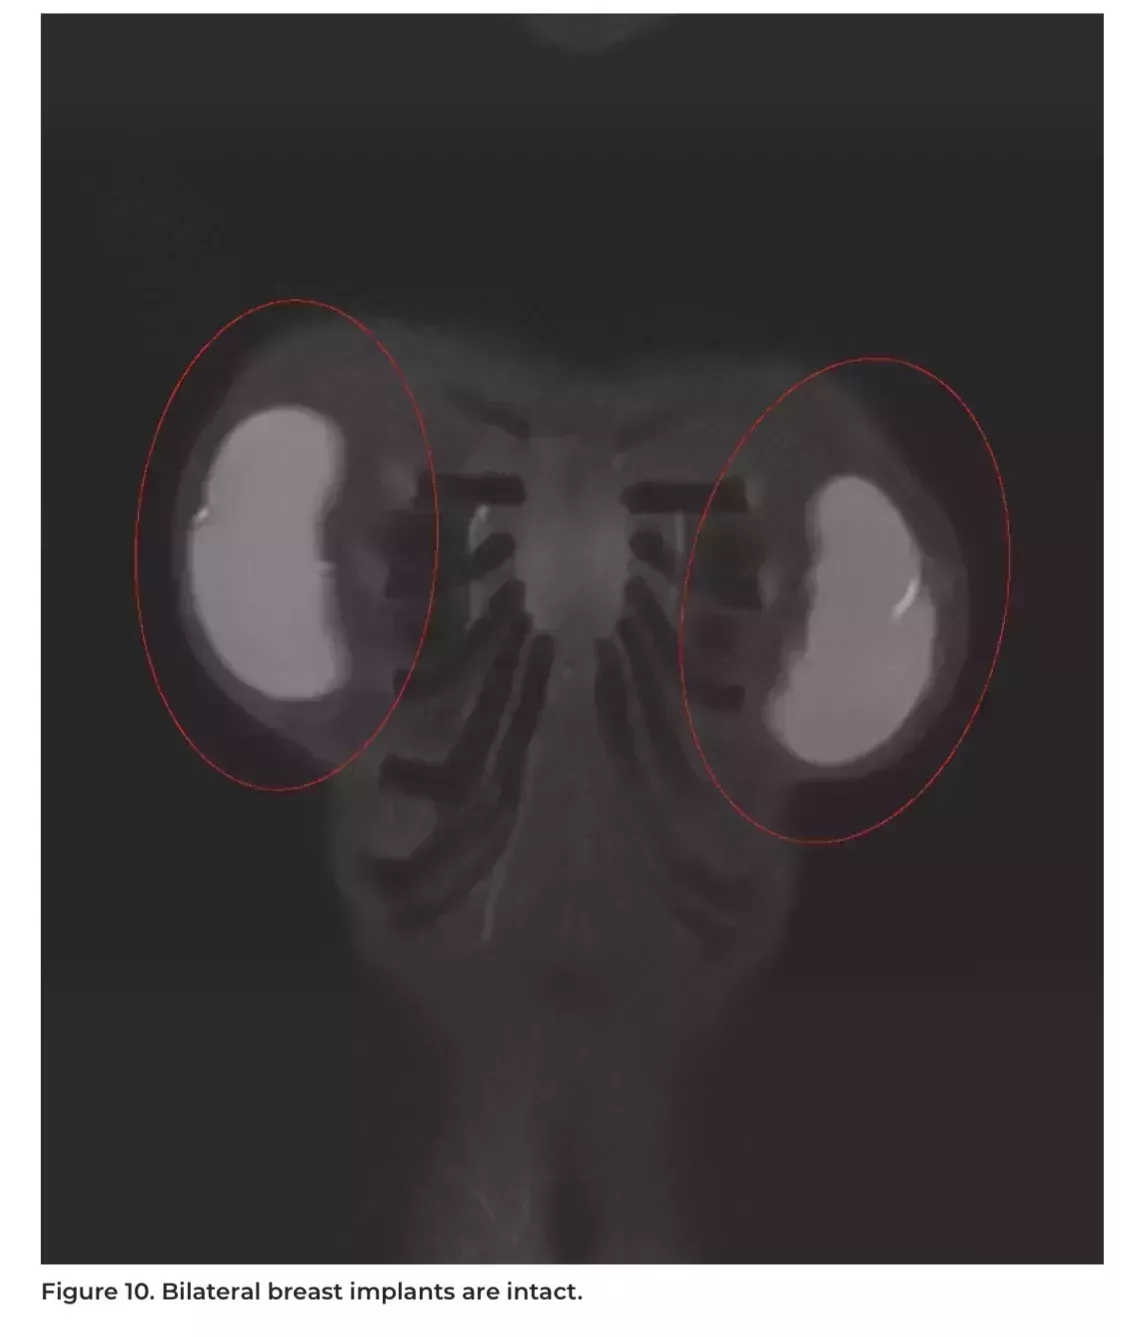

Sarah también dijo que a menudo se pregunta qué pasa con sus implantes mamarios, ya que los ha tenido puestos durante tanto tiempo. Le alegró ver que los resultados mostraban que estaban sanos e intactos. "Mi relación más duradera", como ella dice, sigue siendo sólida.